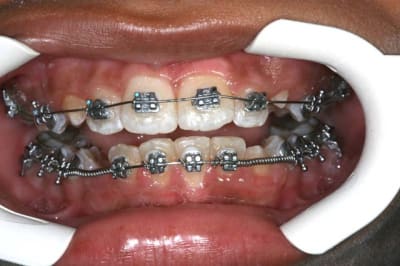

Facile à poser,

Ne retient pas la plaque

Esthétique

Un peu cher car en Or

(Céramco)

un composite d’obturation est très bien toléré, (comme dirait Dancha)

le Pb. est le surcontour.

surcontour d’1 Bk. ou d’une contention sur une face de la dent

plus ce surcontour sera important, plus la plaque se déposera en dessous et sera difficile à éliminer. ici, ce qui me plait est que le surcontour est très fin, mais il existe quand mm. et demande un bon contrôle de plaque.

souvent le composite de recouvrement s’use et la trame des rubans de fibres esthétiques apparaît, les fibres ayant tendance à " rebiquer ", ce qui est un piège à plaque

(je sais, il y en des nouveaux)

dans le cas présenté, lorsque le composite de recouvrement s’usera, ce sera du métal (or) qui sera mis à nu. ceux qui ont vu des stéllites en or dans une bouche comprendront l’avantage sur une fibre en partie effilochée.

et ce qui ne gâte rien, je le trouve très facile à mettre en place, plus facile qu’un ruban, et aussi esthétique

voilà